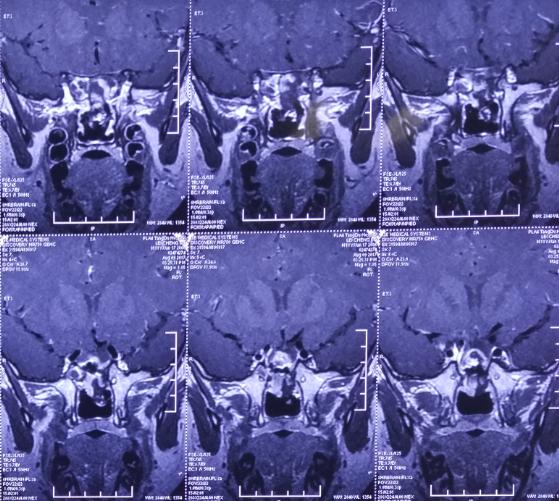

影像资料